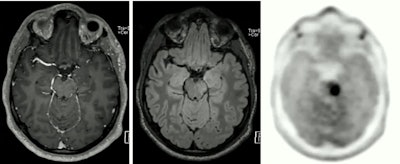

Also, neuro-oncologists use PET/MRI to monitor patients undergoing treatment, primarily to identify glioblastomas that may have returned after surgical removal. Umutlu showed an example of such a case in which MRI alone would probably have missed a tumor, but that was clearly shown with the addition of PET.

The PET component of PET/MRI can reveal brain tumors that may go undetected by MRI alone.

The PET component of PET/MRI can reveal brain tumors that may go undetected by MRI alone."This was one of the cases where the PET component really helped us make a clear diagnosis in terms of a second manifestation of a brain tumor," she said.